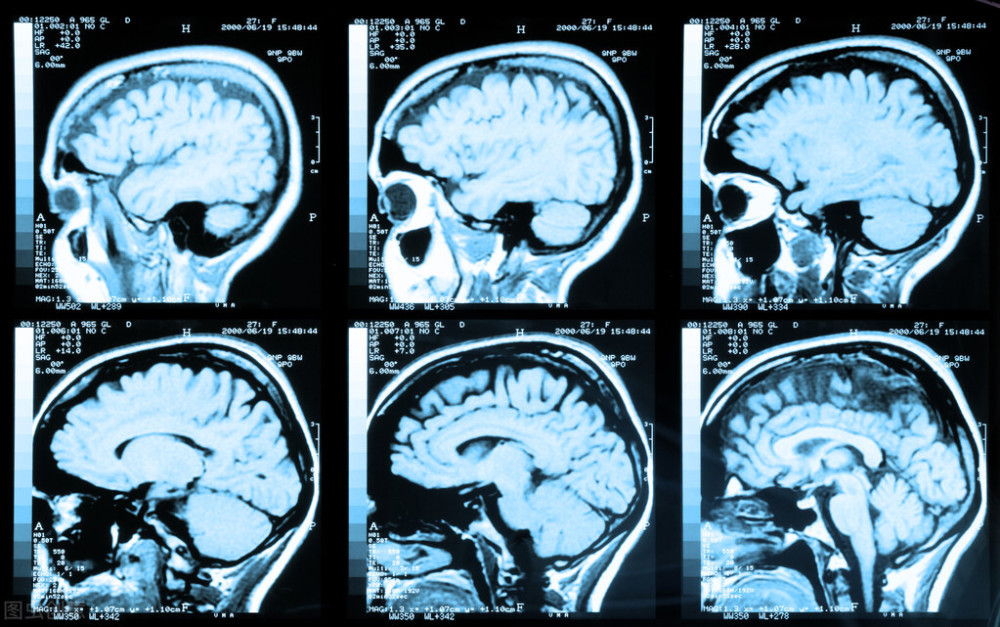

很有必要!根据当时头颅CTA和DSA检查显示,患者前交通动脉微小动脉瘤,直径大概为2mm,瘤壁非常薄。

什么是颅内动脉瘤?

颅内动脉瘤,并不是我们传统意义上的肿瘤。它是我们脑动脉壁上的局部膨出,就好比在血管壁上吹起了小气球,随时会破裂,一旦破裂,对患者带来的危害是不敢想象的。